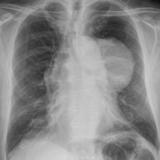

Case 8a Thymoma PA